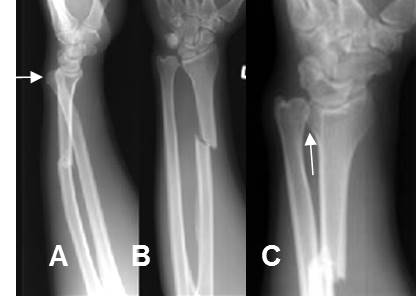

Fig 187. Fractura de Galeazzi.

A: Rx lateral, B: Rx AP y C: Rx oblicua. Fractura espiroidea y algo cabalgada, del radio y luxación en la articulación radioulnar distal.